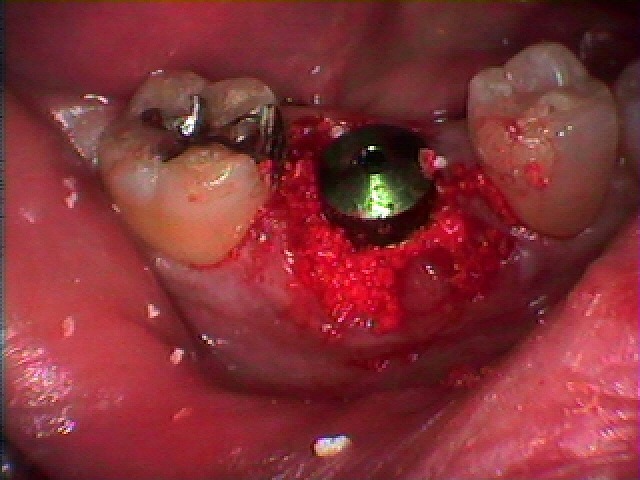

歯を抜かせていただきました

インプラント窩を形成しています

インプラント埋入時になります

骨補填材を転入しています